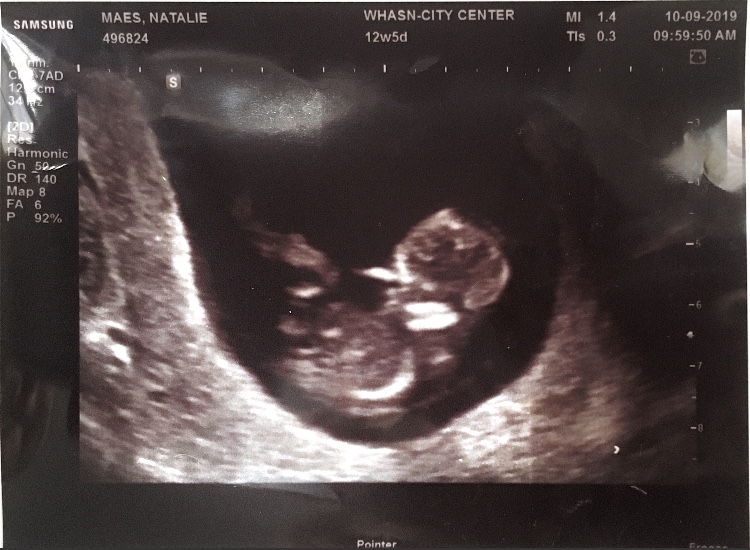

Shortly after finally announcing our pregnancy (I was 12 weeks along so we thought we were safe) we found out that our little one no longer had a heartbeat. It definitely sent our family reeling but we were showered with love and support and time is slowly bringing healing. I've talked and written so much about it that I don't want to say much more in this post, other than to express our gratitude. We are so grateful for everyone who has prayed, spoken with and reached out to us. And we're eternally grateful for our loving Father in Heaven. He has a plan for us and for our little one.